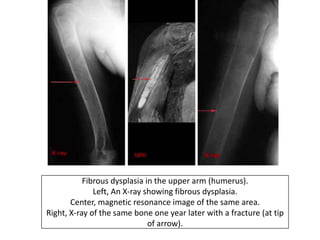

Fibrous dysplasia in the upper arm (humerus).

Left, An X-ray showing fibrous dysplasia.

Center, magnetic resonance image of the same area.

Right, X-ray of the same bone one year later with a fracture (at tip

of arrow).

Fibrous dysplasia inthe upper arm (humerus). Left, An X-ray showing fibrous dysplasia. Center, magnetic resonance image of the same area. Right, X-ray of the same bone one year later with a fracture (at tip of arrow).